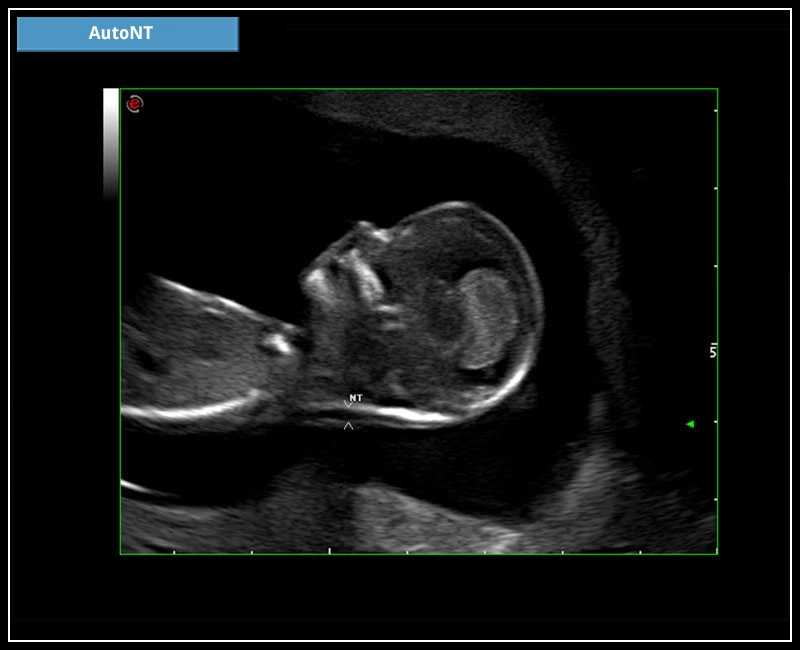

MyLab™9 Platform - HD Zoom on fetus profile with AutoNT measurement

MyLab™9 Platform - HD Zoom on fetus profile with AutoNT measurement

MyLab™X5 - AutoNT

MyLab™X5 - AutoNT

MyLab™X6 - AutoNT

MyLab™X6 - AutoNT

MyLab™X7 - AutoNT

MyLab™X7 - AutoNT

MyLab™Omega - AutoNT

MyLab™Omega - AutoNT